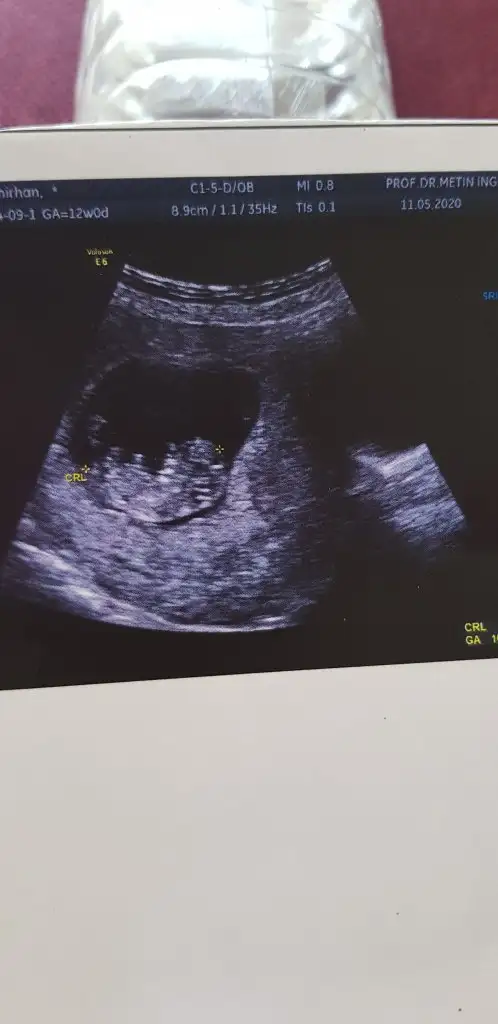

Canım ultrason fotosu varsa atar misin nub una bakalım

Aaa sende anlıyor musun canım ben yüklememiştim dur şimdi yükleyimde bana da bir tahminde bulunan bakalım kızlar heyecan yaptım

Ben burda çok okudum öyle şeyleri. Eğer görebilirsem yorumda bulunabilirim canım. Yolla gelsin